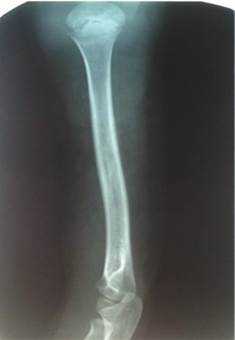

У детей возрастной группы от 3 до 17 лет на 5-7-е сутки болезни рентгенологически деструктивных костных изменений не определялось. Первые рентгенологические проявления в виде увеличения объема и плотности мягких тканей, линейного периостита, нечеткости костной структуры, утолщения и разрыхления коркового слоя отмечались в среднем на 10-14-е сутки (n=43; 39%). Периостит, разрыхление коркового слоя, остеопороз и остеосклероз, деструкция определялись на более поздних сроках. Таким образом, рентгенография не может рассматриваться в качестве метода диагностики остеомиелита на ранних сроках (рис. 1).

Рис. 1. Острый гематогенный остеомиелит плечевой кости - 11-е сутки заболевания